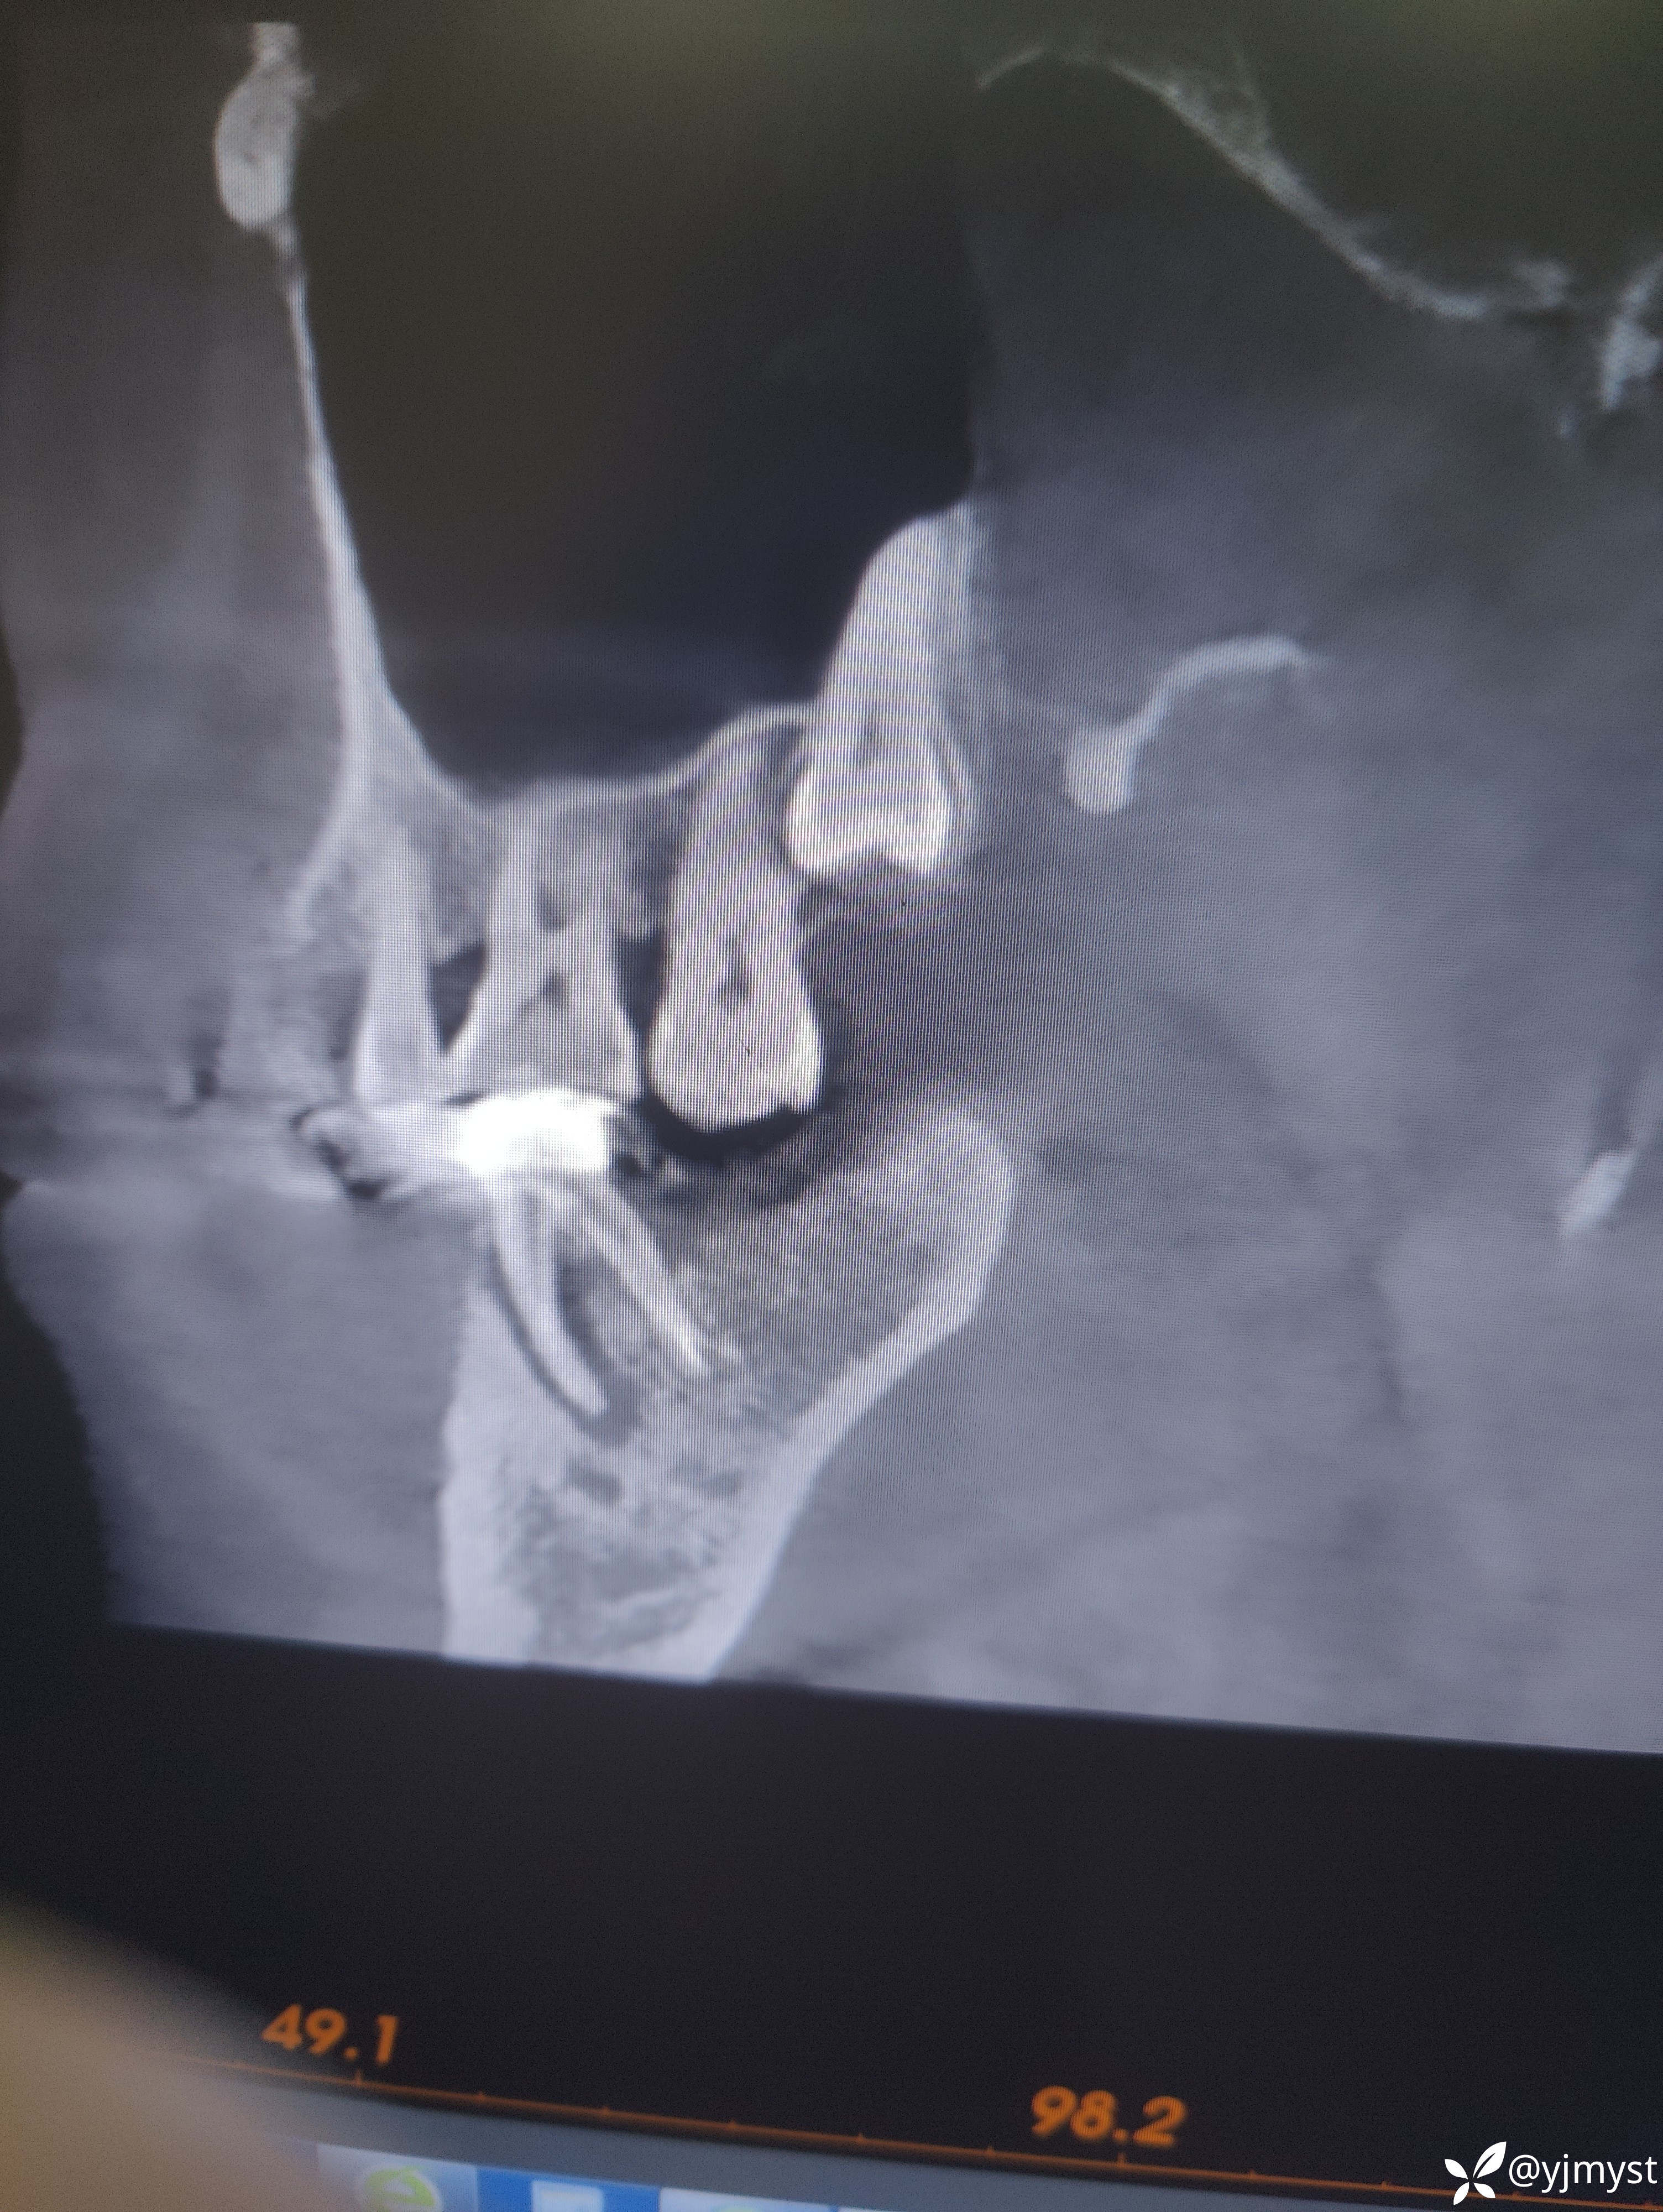

检查发现45牙、46牙LAVA联冠,无松动,拍CT示46牙近中根根周暗影,补拍一张瘘管插入牙胶尖的小牙片发现牙胶尖在近中牙根下段弯曲了,近颊某个位点牙周袋探诊深度为7mm,叩诊稍有不适,诊断牙周牙髓联合病变。跟患者交流说怀疑脓包来源可能既有牙周也有根管原因,提出了3个方案:①根管再治疗+牙周刮治②根尖手术进行倒预备倒充填③拔除做种植。